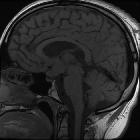

MRI

MRI is the most useful imaging modality for evaluating LCH CNS involvement . Similar to the clinical presentations, three groups of neuroimaging features may be appreciated, which again may or may not all be present in any given patient .

Neurodegenerative changes

These are the second most common CNS manifestation of LCH . Patients with neurodegeneration demonstrate bilateral symmetric parenchymal lesions of the cerebellum (especially the dentate nuclei) and basal ganglia, however uncommonly other regions of the brain and brainstem (especially the pons) may be affected and cerebral atrophy may also be noted . These affected regions often initially demonstrate T1-weighted high intensity with variable T2-weighted intensity, however progress to marked T2-weighted high intensity . Contrast enhancement can also be variable throughout the temporal progression of the disease .